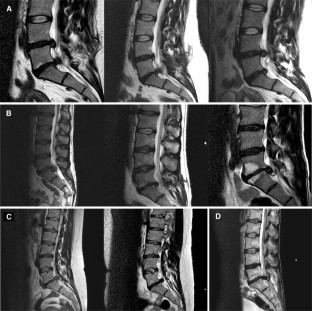

Fig. 1

Fig. 2

Fig. 3

Fig. 4

Fig. 5